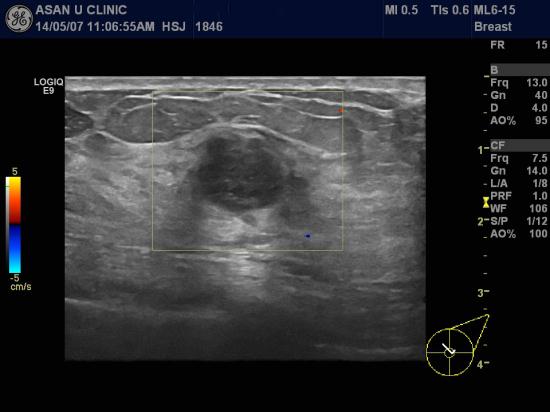

좌측 유방에 몽우리가 갑자기 만져져 내원하신 56세 여성분입니다.

2년전에 유방검진-공단에서 실시하는 유방촬영상에는 이상이 없었다고 하십니다.

검사당시 좌측 유방에 1.48cm의 작지 않은 혹이 있었고,

같은 쪽 겨드랑이에 네개이상의

림프절비대 소견이 있었습니다.

조직검사로 좌측유방의 침윤성 유관암 진단되었으며,

겨드랑이의 림프절에서 또한 전이된 암세포가 진단되었습니다.